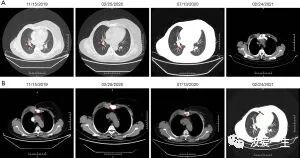

2019年7月,患者发现右胸壁肿块,弥漫性水肿,皮肤发红。随着肿块逐渐进展,患者于2019年11月11日入院湖南省肿瘤医院进行检查和治疗,ECOG评分显示体力状态(PS)为0。B超检查显示内外科有异质性肿块右胸壁疤痕;右侧锁骨上区低回声结节,被认为是淋巴结肿大;左乳房小叶增大;腋窝及左侧锁骨上区均未见明显肿大淋巴结。计算机断层扫描 (CT) 显示右侧胸骨上有一个 3.3 cm × 3 cm 的肿块,伴有骨质破坏,双肺转移,最大直径达 1 cm,纵隔淋巴结肿大(图1)。2019年11月15日,当地医院病理切片IHC显示c-erbB-2 2+、ER 80%、PR 80%、Ki-67 40%(图2)。2019 年 11 月 22 日,对胸壁肿块进行了空芯针活检,发现低分化乳腺癌衍生癌。这得到了患者病史和 IHC 结果的支持(c-erbB-2 2+,ER 80%,PR 80%,Ki-67 40%;图 3)。荧光原位杂交 (FISH) 未发现 HER2 扩增(图 4)。综合以上资料,患者经改良根治术确诊为复发性右乳癌,右胸骨量大,骨质破坏,胸壁及双肺转移。

图1病变的计算机断层扫描(CT)图像(箭头所示):(A)胸骨转移;(二)肺转移。

患者随后从 2019 年 12 月 3 日开始单独服用吡罗替尼(每天 400 毫克,每 4 周一次)和来曲唑(每天 2.5 毫克,每 4 周一次)。2020 年 1 月 29 日,右肺转移灶明显缩小经 CT 确认并被评估为部分缓解(图 5)。由于 COVID-19 大流行,该方案于 2020 年 2 月 2 日至 2020 年 2 月 11 日停止。